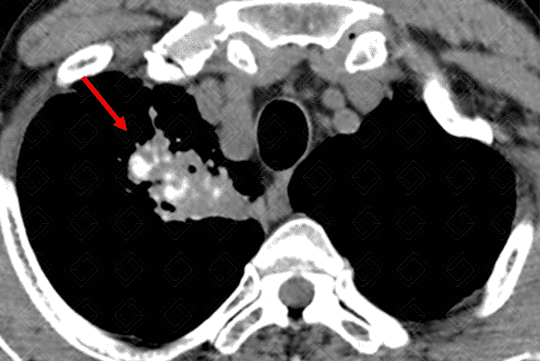

Texto alternativo para a imagem Figura 3 - Créditos: Dra Elazir Mota - Rio de Janeiro/RJ

Na janela de partes moles, as calcificações no interior das opacidades são melhor apreciadas (seta vermelha - figura 3), bem como os linfonodos calcificados no mediastino e hilo pulmonar (cabeça de seta - figura 4).